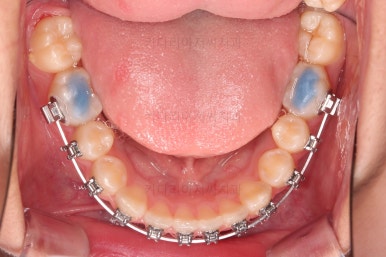

초진 시 입안의 모습입니다.

눈에 띄는 부분은 당연히 앞니가 삐뚤고, 앞니 하나가 앞으로 튀어나온 모습인데요.

자세히 관찰해 보면 다른 문제점들이 보입니다.

우선 위아래 앞니가 깊숙히 맞물려 있는 과개교합 양상인데요.

악궁확장부터 시행합니다.

확장이 잘 되어 앞니 사이에 틈새도 잘 벌어진 것이 확인되고요.

적절한 시기에 시차를 두고 순차적으로 브라켓을 부착합니다.

이번 환자분이 선택한 브라켓은 자가결찰 메탈의 한 종류인 엠파워 메탈 장치였습니다.

적절한 시기에 아랫니도 장치를 구성하고요.